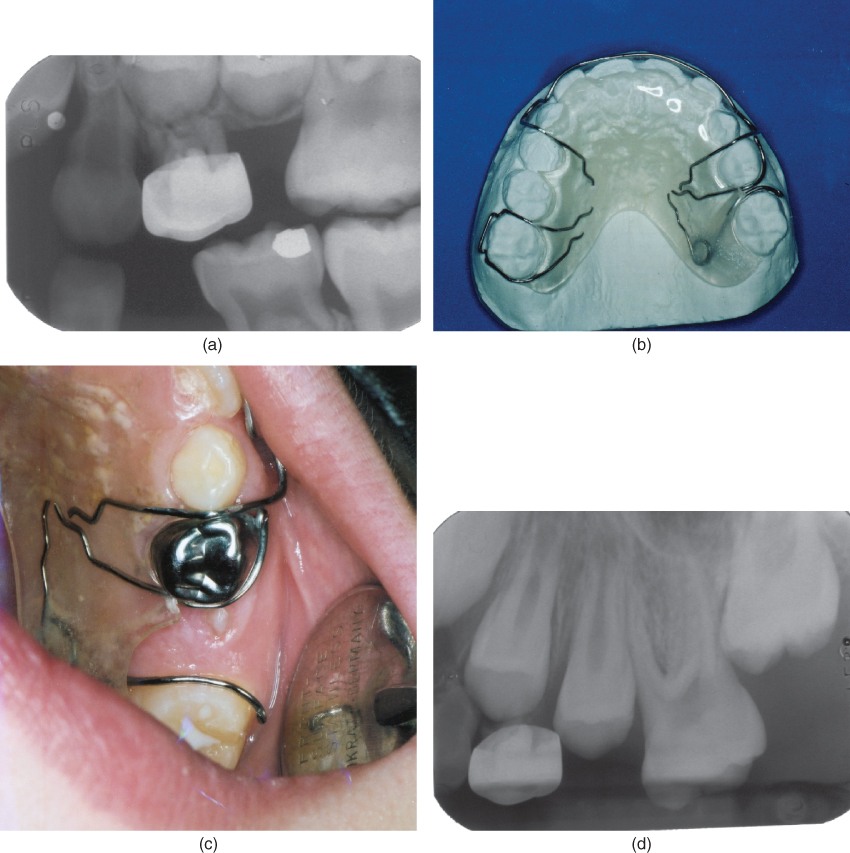

Correction of ectopic eruption of permanent molars utilizing the brass Brass Wire Ectopic Eruption Ectopic eruption (ee) is defined as a localized disturbance in the eruption path of a tooth leading to an abnormal position or orientation of that tooth. Ee of permanent first molars is observed when the molar assumes an abnormal mesioangular path of eruption, resulting in an impaction at the distal aspect of the primary second molar. Ectopic eruption of a. Brass Wire Ectopic Eruption.

Brass wire ligation for treatment of the ectopic eruption of the Brass Wire Ectopic Eruption Ee of permanent first molars is observed when the molar assumes an abnormal mesioangular path of eruption, resulting in an impaction at the distal aspect of the primary second molar. Ectopic eruption (ee) is defined as a localized disturbance in the eruption path of a tooth leading to an abnormal position or orientation of that tooth. Ectopic eruption of permanent. Brass Wire Ectopic Eruption.

Figure 1 from Correcting ectopic first permanent molars with metal or Brass Wire Ectopic Eruption Ectopic eruption of permanent molars is one of the challenges that arise in the early mixed dentition period, particularly when the root of the primary. Ee of permanent first molars is observed when the molar assumes an abnormal mesioangular path of eruption, resulting in an impaction at the distal aspect of the primary second molar. Ectopic eruption of pmfm is. Brass Wire Ectopic Eruption.